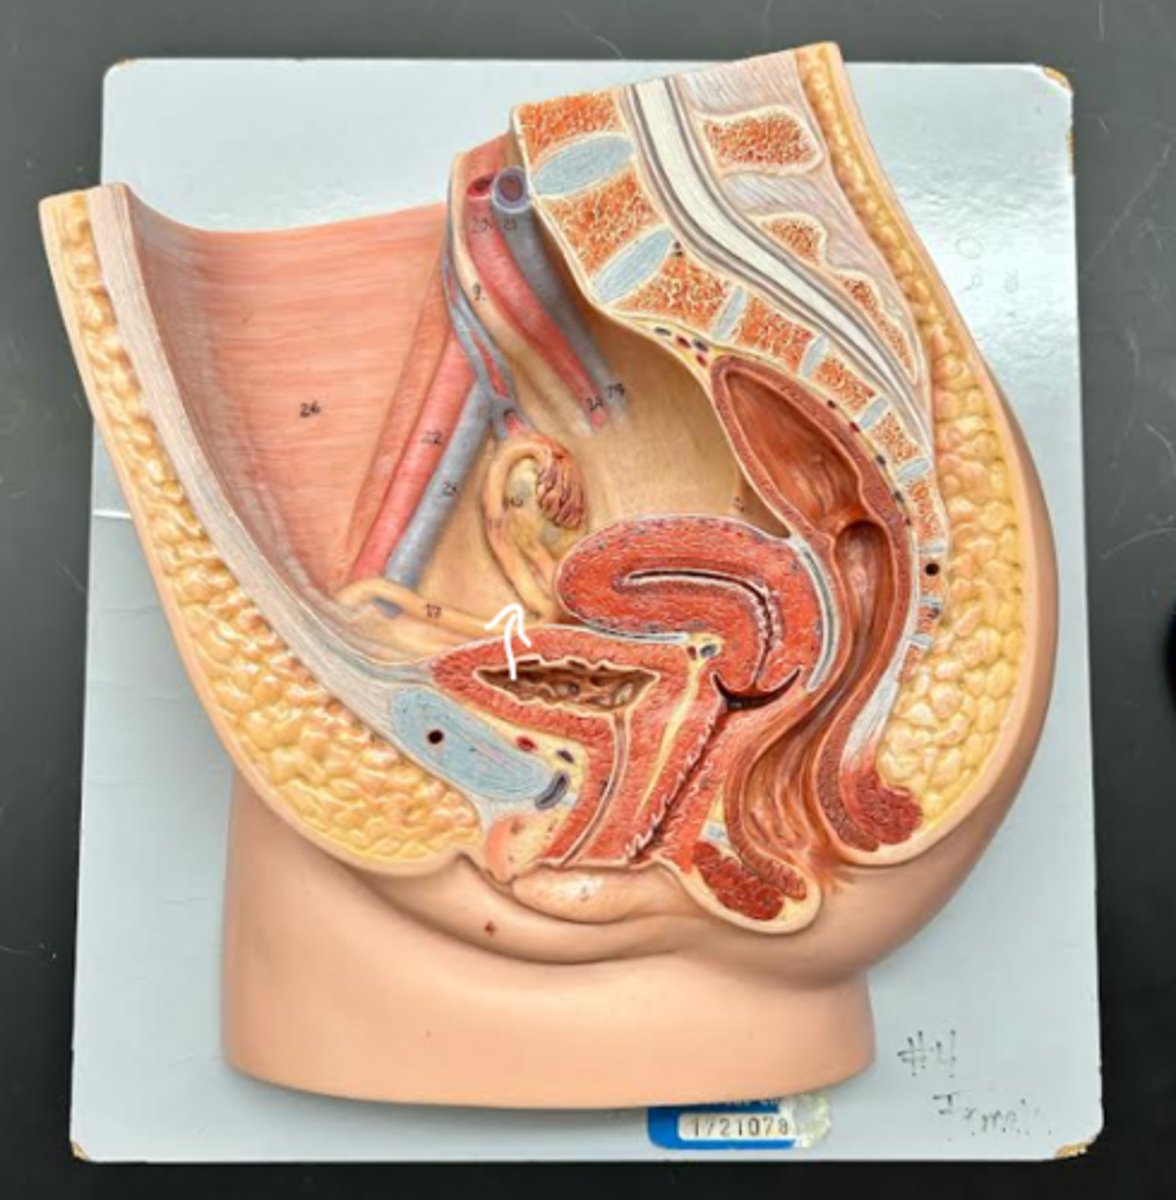

Vagina

Vaginal orifice

Hymen

Vaginal fornix

Uterus

Fundus

Body of uterus

Cervix

Internal os

Cervical canal

External os

External urethral orifice